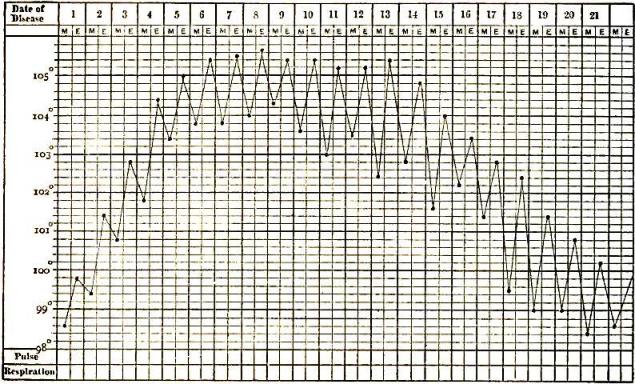

| 12. | CHART OF TYPICAL RANGE OF TEMPERATURE IN TYPHOID FEVER, AFTER WUNDERLICH |

| 13. | CHART SHOWING RECRUDESCENCE OF FEVER FROM INDISCRETION OF DIET |

| 14. | CHART SHOWING FALL OF TEMPERATURE FROM INTESTINAL HEMORRHAGE IN TYPHOID FEVER |

| 15. | PULSE-TRACING IN RELAPSES OF TYPHOID FEVER |

Of all these manifold evidences of fever, the elevation of temperature is the one whose cause, range, and results have been most carefully and critically investigated. No record of a case in which fever is present is regarded as complete without the chart of the daily variations in temperature, respiration, and circulation. The practical value of such records is thus admitted, and in the experiments relating to the origin of animal heat the observations of temperature are as essential as the chemical analyses, each of which supplements the other.